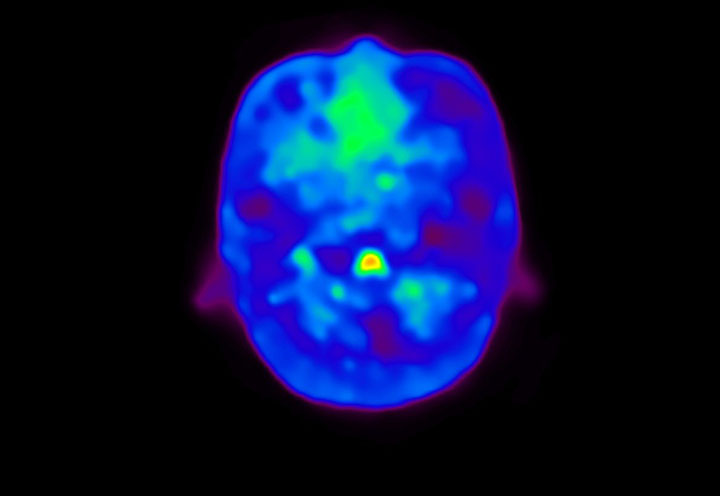

Head / Case4 : Amyloid

Axial

Courtesy : Kindai University Hospital

- Imaging protocol

- Injected dose: 3.21 MBq/kg, 18F-Flutemetamol

- Uptake time: 100 minutes

- Scan time: 20 minutes